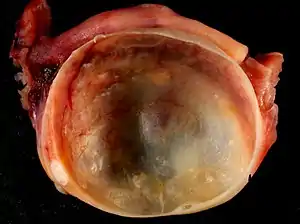

![]() На знімку зображений макропрепарат кісти яєчника На знімку зображений макропрепарат кісти яєчника | |